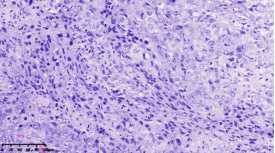

在本项研究中,研究人员利用基本的组织形态学方法及免疫组织化学法对TNBC进行分型:腔面雄激素受体型(LAR)(图1A),免疫调节型(IM)(图1B),基底样免疫抑制型(BLIS)(图1C),间充质型(MES)(图1D)。评价各亚型临床病理参数(如发病年龄、肿物大小、淋巴结转移等),组织形态学(肿物中央瘢痕形成、浸润模式、肿瘤间质浸润淋巴细胞、细胞排列方式、细胞核形态、核分裂计数、间叶化生等)以及免疫表型(p53、Rb、PD-L1、MMR等),结果显示:1.TNBC分型的临床病理、组织形态学和免疫表型特征不尽相同,有望成为复杂的基因表达谱分析的替代选择,为TNBC的分型治疗及靶向治疗提供理论依据;2.生物标记物 PD-L1作为重要的生物学指标,对个体化治疗及免疫治疗有重要的临床指导价值;3.乳腺癌中dMMR作为一个低频发生事件,不太可能作为免疫治疗有效性的评估手段。该成果发表在Virchows Archiv期刊,题目为“Subclassifying Triple-Negative Breast Cancers and Its Potential Clinical Utility”。文章DOI为:10.1007/s00428-022-03329-0。

图1. 基于组织形态学及免疫组织化学标记物的TNBC分型